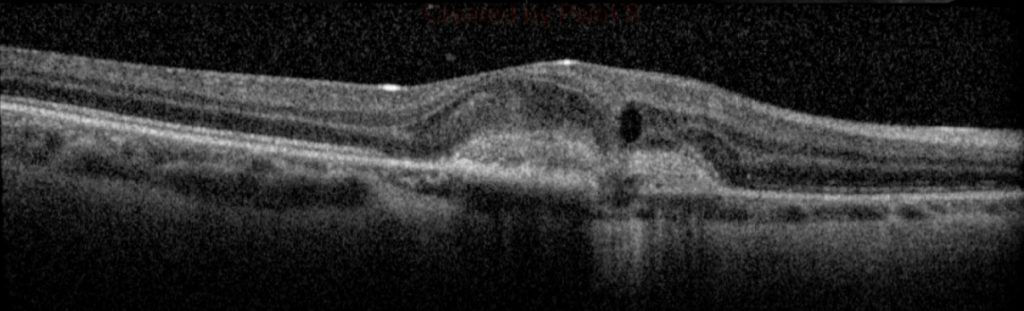

A 26-year-old healthy Hispanic-American female who grew up in the Ohio Mississippi River Valley presented with a two-month history of decreased vision involving the right eye described as a stationary “central spot”. Her past ocular history was significant for myopia OU. On examination, visual acuity with correction was count fingers at 3 feet OD and 20/40 OS. Fundus examination OU showed no vitreous cell or haze with tilted optic nerves and peripapillary atrophy. Fundus exam was significant for wide-spread chorioretinal scarring OD (Figure 1). Retinal findings were purely unilateral. Fluorescein angiography demonstrated staining of the multifocal scars scattered throughout the fundus with leakage from the juxtafoveal scar concerning for an active choroidal neovascular membrane (CNVM). Optical coherence tomography (OCT) showed subretinal hyperreflective material with intraretinal fluid OD (Figure 2).

The patient received an intra-vitreal bevacizumab injection OD. Four weeks later, vision was unchanged with development of a serous pigment epithelial detachment (PED) in association with the prior observed fibrovascular CNVM. Further injections were not recommended as the visual gain was minimal due to chronicity of the CNVM given the fibrotic response. At recent examination, one-year post-presentation, there was minimal coalescence of the fibrovascular CNVM and PED, and vision has remained stable.